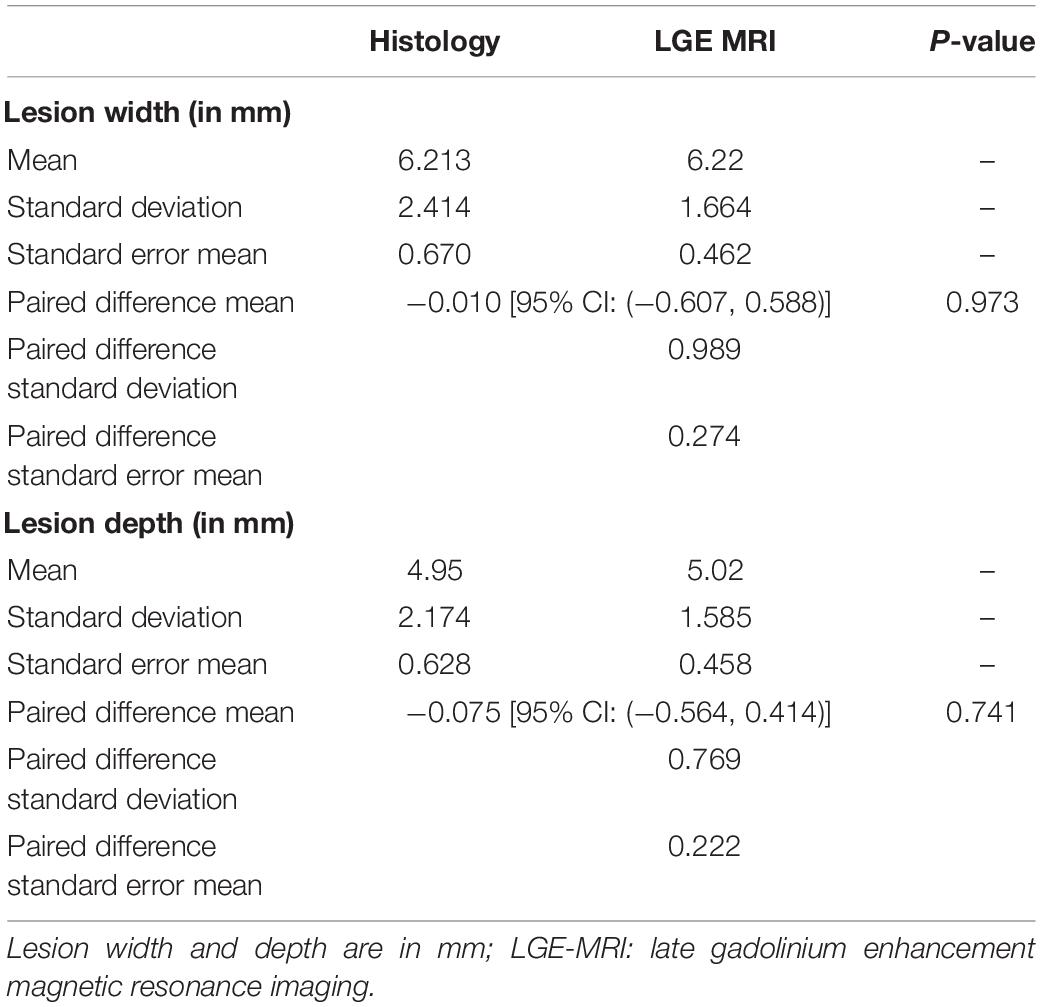

c- Comparison between LGE-MRI lesions and pathological assessment post necropsy

The similarity between LGE-MRI and pathological assessment can be seen in Figure 4. Maximal lesion depth and width seen on histology as compared to LGE-MRI are summarized in Table 2. There was no statistically significant difference between histological findings and LGE-MRI measurements (p = 0.973 for width; p = 0.741 for depth).

Figure 4. Images of two connected lesions in the RV free wall shown on LGE-MRI and corresponding Corview reconstructions in the acute phase [(A): axial view and (D)] and the chronic phase [(B): axial view and (E)]. Note the similarities between LGE-MRI in the chronic settings (B) and pathological assessment (F). Images of two unconnected lesions in the LV free wall shown on LGE-MRI and corresponding Corview reconstructions in the acute phase [(G): axial view and (J)] and the chronic phase [(H): axial view and (K)]. Note the similarities between LGE-MRI in the chronic settings (H) and pathological assessment (L). Images (C) and (I) are zoomed in figures of B and H, respectively.

Table 2. Comparison of acute and chronic lesion measurements obtained using LGE-MRI and histological assessment.

We also included Bland Altman Plots as a Supplementary Figure 1 to compare LGE-MRI and pathological assessment of lesions.